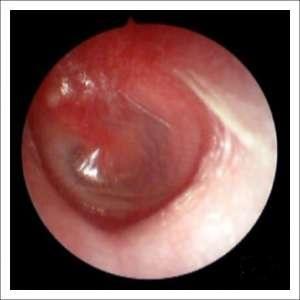

| Эндоскопия носа и пазух | Визуальный осмотр слизистой, выявление грибковых масс. | Позволяет оценить степень поражения и взять материал для анализа. |

Перед тем как назначить необходимое лечение, врач проводит диагностику заболевания. Этот процесс включает не только визуальный осмотр, но и рентгенографию, а также компьютерную томографию.

| КТ или МРТ пазух | Определение распространенности процесса, наличия деструкции костей. | Необходимы для планирования хирургического вмешательства. |